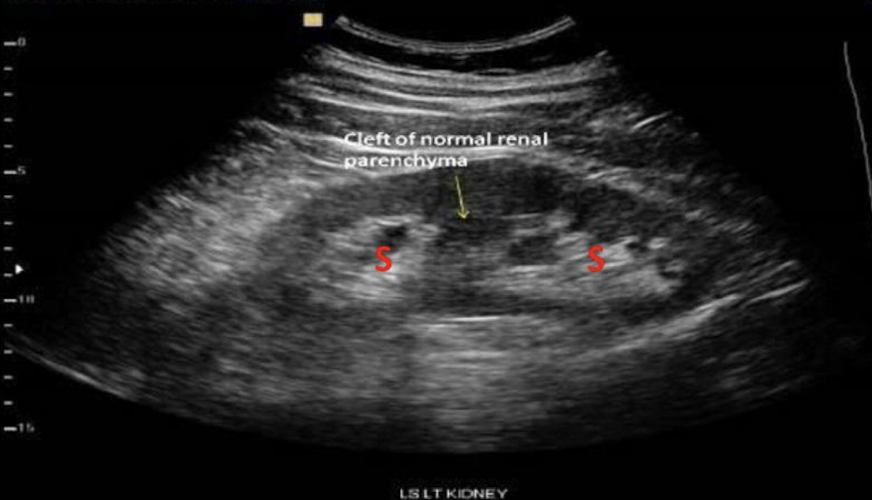

What does CB stand for in this image?

Column of Bertin

Prominent Columns of Bertin can be mistaken for:

a renal mass